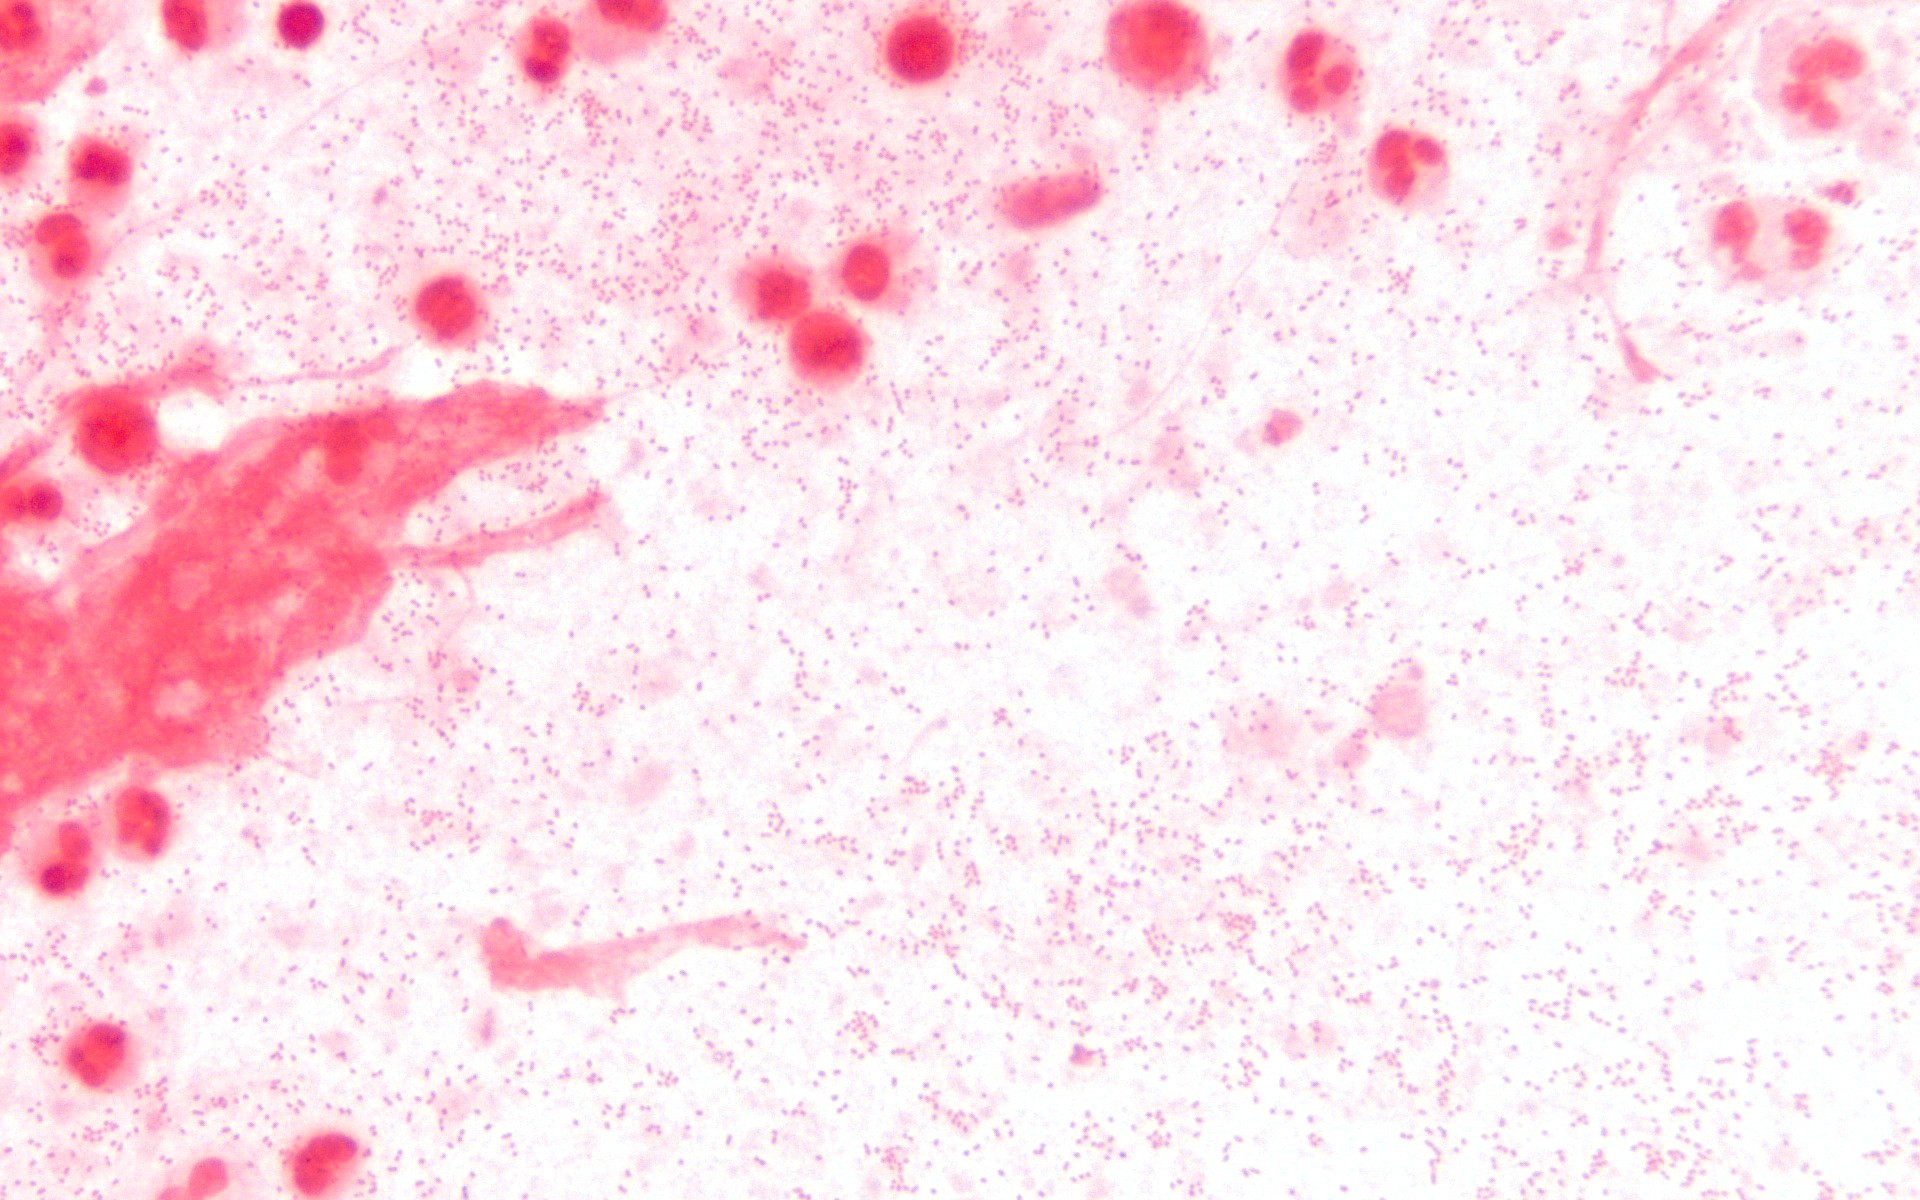

그람 염색 후 현미경으로 관찰하면 그람 음성 구간균으로 나타난다. 카탈레이스와 산화 효소 검사를 통해 추가로 특정할 수 있으며, 두 검사 모두 양성이어야 한다.[90]

그람 염색 후 현미경으로 관찰하면 그람 음성의 구간균으로 나타난다.[90] 카탈레이스와 산화 효소 검사를 사용하여 추가로 특정될 수 있으며 둘 다 양성이 나와야 한다.[90]

침습성 ''H. influenzae'' 감염은 세균 배양, 라텍스 응집 검사, 중합효소 연쇄 반응 검사 등으로 확진한다. 비인두강이나 인후에서 배양된 ''H. influenzae''는 질병을 의미하지 않지만, 뇌척수액, 혈액, 관절액 등에서 분리된 경우는 침습성 감염을 나타낸다. 그람 염색 표본을 현미경으로 관찰하면 그람 음성 코코바실러스가 보이며, 카탈라아제 및 옥시다아제 검사에서 모두 양성 반응을 보인다. 추가적인 혈청학적 검사를 통해 캡슐 다당류를 구별하고 ''H. influenzae'' b형과 비피막 균주를 구별할 수 있다. 세균 배양은 특이적이지만 민감도가 낮아, 검체 채취 전 항생제 사용은 세균 분리율을 감소시킬 수 있다.[37]

- 배양된 균은 그람 염색 후 현미경으로 관찰하면 그람 음성의 구간균으로 나타난다.[90]